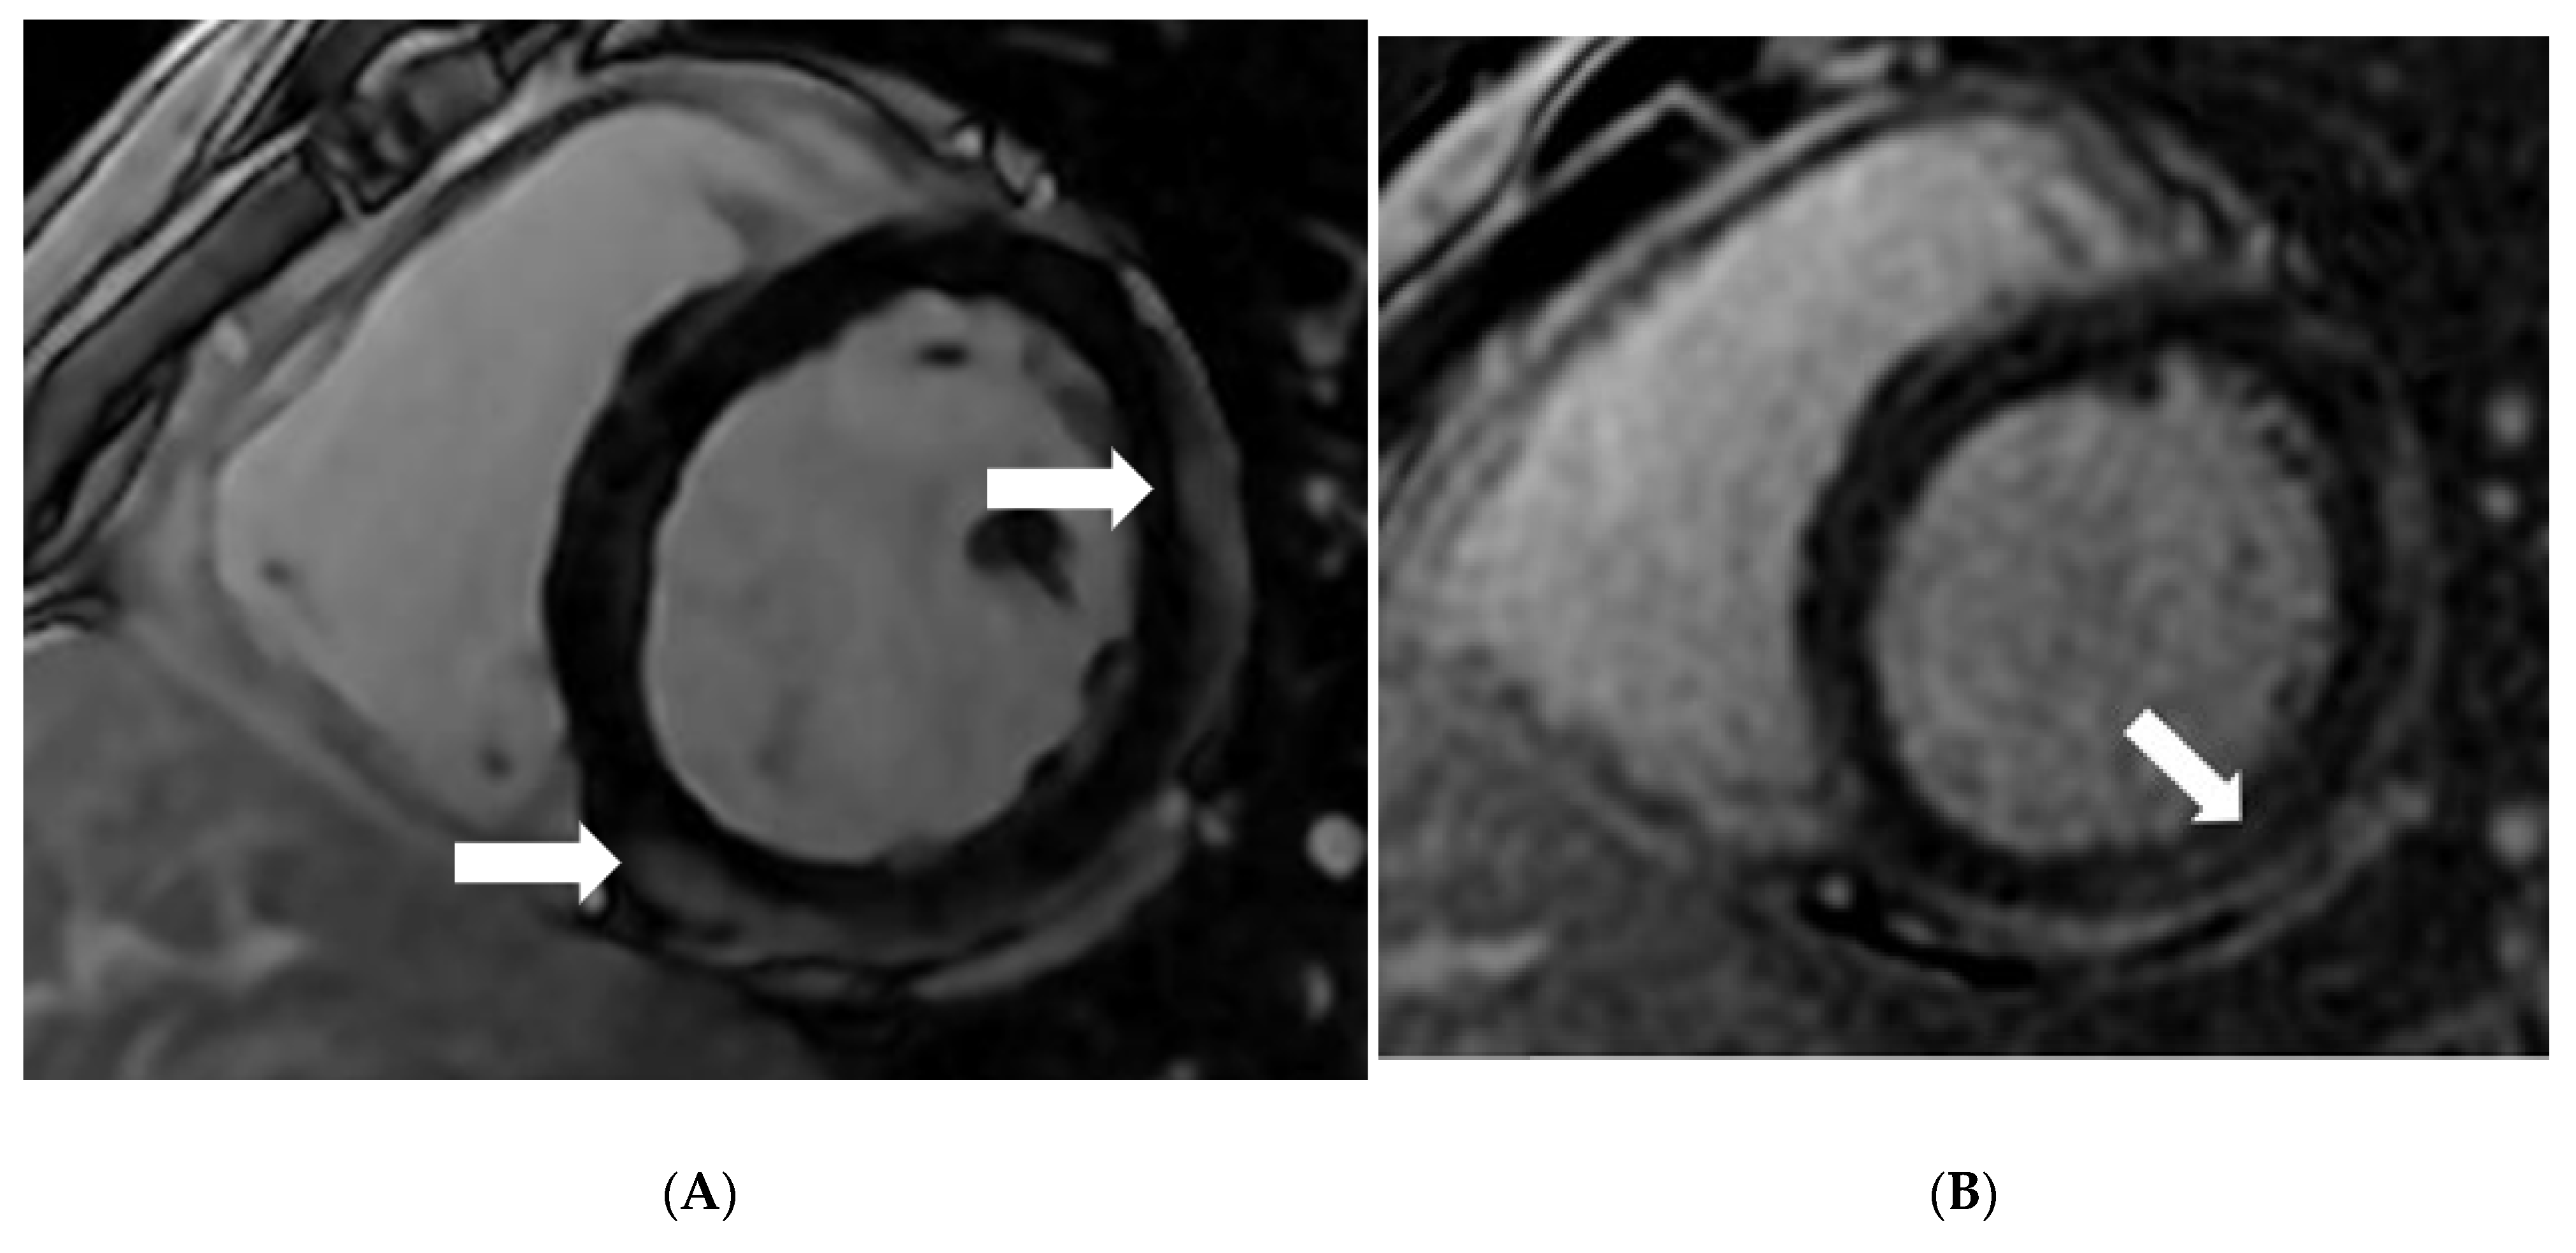

Post-RNA (mRNA) Vaccination Myocarditis: CMR Features

Das, K.M.; Mansoori, T.A.; Shamisi, A.A.; AlBastaki, U.M.; Gorkom, K.V.; Alkoteesh, J.A. Post-RNA (mRNA) Vaccination Myocarditis: CMR Features. Diagnostics 2022, 12, 1034. https://doi.org/10.3390/diagnostics12051034